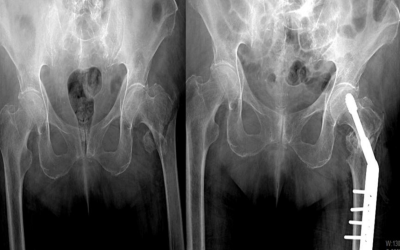

El poder de GeneX (β-TCP/CaSO₄) para tratar fracturas de cadera inestables

Las fracturas intertrocantéricas inestables (fracturas de cadera) en pacientes mayores de 65 años continúan representando un reto terapéutico por su alta tasa de complicaciones y el riesgo de falla mecánica del implante. El estudio elaborado por el Vélez de Lachica et…